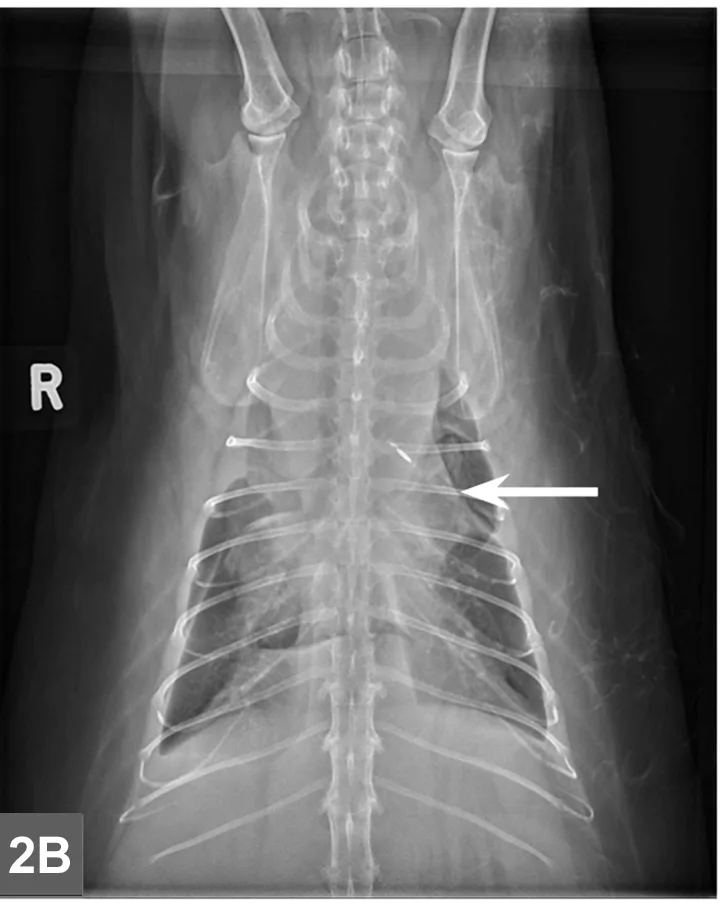

Featured Image

FIGURE 2C

Cranial mediastinal mass in a cat.Thoracic ultrasound demonstrates an irregularly marginated, hypoechoic mass within the cranial mediastinum surrounded by a small-volume pleural effusion within the left and right hemithoraces (ventral to the left in image). Image and description courtesy of Christopher T. Ryan, VMD, DABVP, DACVR, Hope Veterinary Specialists.

Mediastinal

• Typically localized form of LSA involves infiltration of the thymus and/or cranial mediastinal and sternal lymph nodes with intermediate to large neoplastic lymphocytes with signs related to the intrathoracic mass effect and secondary pleural effusion (Figure 2).

• Thoracic radiographs may reveal a mediastinal mass effect.1-4

• Ultrasound can be used to visualize the cranial mediastinum and may reveal a hypoechoic mass or cluster of enlarged lymph nodes (Figure 5, see gallery).